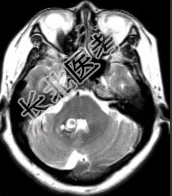

- 简答题4、MR增强检查如下图。请问最可能的诊断是什么?

关注下方微信公众号,搜题查看答案